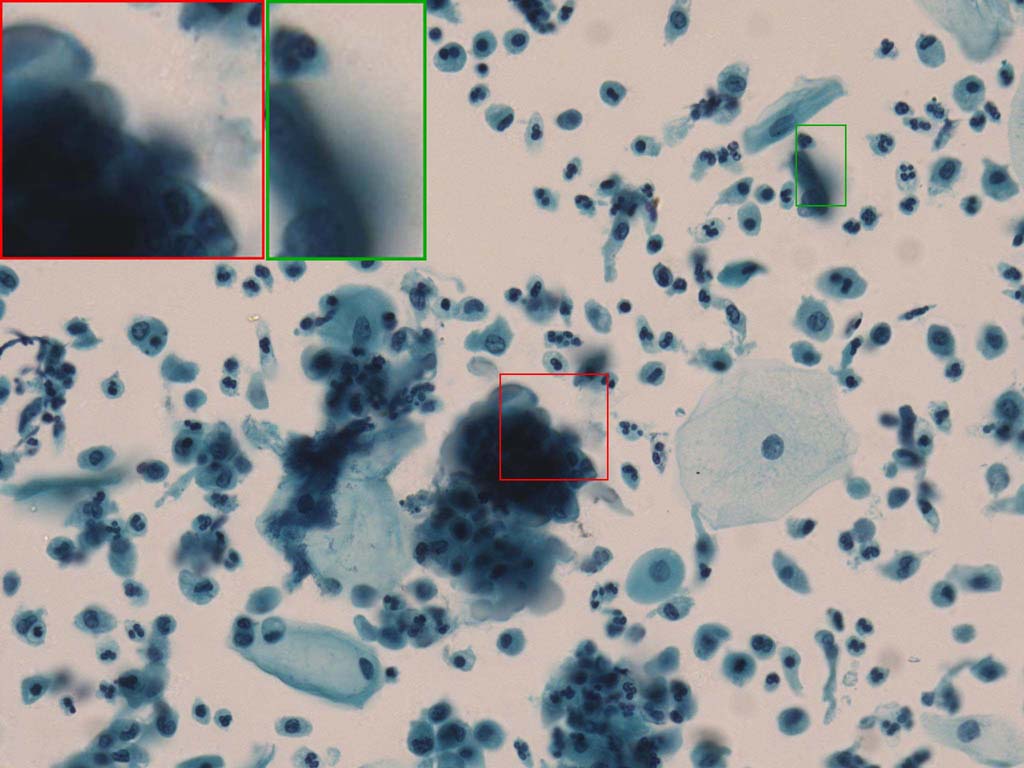

To demonstrate the effectiveness and efficiency of the proposed image fusion method , we conduct a set of comparative experiments on three image datasets. The first is composed by 8 pairs of multi-modal medical images and the second one contains 15 pairs of multi-focus gray or color natural images. These two datasets are often used in many related papers and some examples are shown in Figure 3(a) and Figure 3(b). The third one is a new multi-focus cervical cell image dataset collected by ourselves, which consists of 15 groups of color images and each group contains a series of multi-focus cervix cell images with size of or , etc. Some source examples are shown in Figure 3(c). Our source code implemented in C++ along with the new multi-focus cervical cell image dataset is available online.

Figure 9, Figure 10 and Figure 11 show the comparative fused results of the multi-focus cell images shown in Figure 3(c). For clarity, we also present a closeup view in the right-bottom of each sub-picture in Figure 9 and Figure 10. As shown in the close-up views of Figure 9, the fused images based on DSIFT, IM, MWGF and BF methods are extremely blurred in the boundary and fail to keep the details of cell nucleus. Furthermore, the DTCWT and NSCT based methods produce halo artifacts in the fused images, while GFF and CNN based methods fail to preserve the small cell nucleus. LP-SR based method nearly works fine which keeps the most of the details of the small size cells, but the integrity of the clustered large size cells is damaged. Fortunately, in our proposed method, the integrity of the clustered large size cells is preserved and most of the isolated small size cells are maintained from the original images, which demonstrates the best visual quality.

Similarly, as shown in the close-up views of Figure 10, the fused images from DSIFT, IM, MWGF and BF are blurred and lose some nucleus details, while the results from DTCWT, GFF, CNN and NSCT produce halo artifacts. LP-SR based method can keep details well but also produces halo artifacts and other noise. Our method can preserve the focused areas of different source images well without introducing any artifacts. For the example illustrated in Figure 11, the fused images generated by DSIFT, DTCWT, IM and NSCT all fail to preserve the focused areas of different source images and result in extremely blurred images. The GFF, CNN, MWGF and BF based method introduces a lot of color distortion of the nucleus regions and the obvious halo artifact. The result of LP-SR based method is close to the one of our method but introduces some odd color distortion. Again, our method produces fused image which can preserve the focused areas of different source images well without introducing any artifacts.